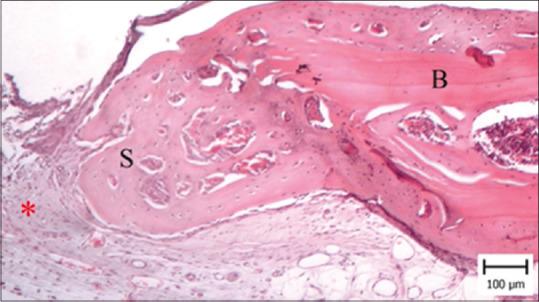

Fifteen adult female Wistar rats weighing approximately 200 g were used and 8 mm in diameter defects were created in their calvaria. The rats were divided into three groups: 1.2% melatonin gel, 5% melatonin gel, and the control group. The animals were sacrificed after 4 weeks. Hematoxylin and eosin staining were used to prepare histological sections. Statistical analysis was performed using the Analysis of variance and Tukey's test. < 0.05 was considered significant.

The results showed a significant difference in rate of ossification ( < 0.001), area of new capillaries ( = 0.002), and mean degree of inflammation ( < 0.001) between the three groups. Comparing groups pairwise, degree of inflammation ( = 0.003) and area of new capillaries ( = 0.019) were significantly lower in the 5% melatonin gel group than the 1.2% melatonin gel group ( = 0.003). The percentage of ossification was substantially greater in the 5% melatonin gel group than in the control and 1.2% melatonin gel groups ( < 0.001).

Within the limitations of this animal study, our findings revealed that melatonin gel can be used as a stimulant of bone formation. Outcomes in this study show increased percentage of ossification in the melatonin groups when compared with the control, in a dose-dependent manner, as 5% melatonin gel has a greater effect on ossification.

选用15只体重约200 g的成年雌性Wistar大鼠,在其颅骨上制造直径8 mm的缺损。将大鼠分为三组:1.2%褪黑素凝胶组、5%褪黑素凝胶组和对照组。4周后处死动物。用苏木精和伊红染色制备组织学切片。采用方差分析和Tukey检验进行统计分析。P<0.05被认为具有显著性。

结果显示,三组之间的骨化率(P<0.001)、新毛细血管面积(P=0.002)和平均炎症程度(P<0.001)存在显著差异。两两比较各组,5%褪黑素凝胶组的炎症程度(P=0.003)和新毛细血管面积(P=0.019)显著低于1.2%褪黑素凝胶组(P=0.003)。5%褪黑素凝胶组的骨化百分比显著高于对照组和1.2%褪黑素凝胶组(P<0.001)。

在本动物研究的局限性内,我们的研究结果表明褪黑素凝胶可作为骨形成的刺激剂。本研究结果显示,与对照组相比,褪黑素组的骨化百分比增加,呈剂量依赖性,因为5%褪黑素凝胶对骨化的影响更大。